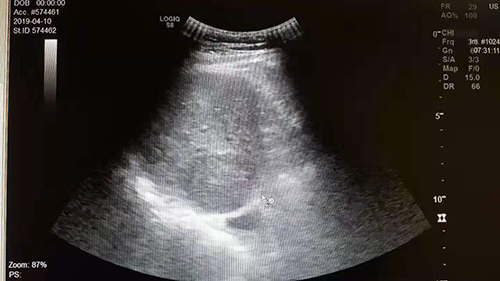

美超体检中心客户、男性、65岁,有“小三阳”多年。2019年5月体检,超声和CT影像学均显示肝血管瘤,并与去年比较结果相同,肿瘤指标甲胎蛋白检查显示阴性。超声与CT图像在比较分析时发现,超声与CT初步判读的肝血管瘤并不在肝脏的同一部位(同一病灶),经对病灶进行定点超声扫查,确认为肝实质性占位,随后在东方肝胆医院获得手术切除。